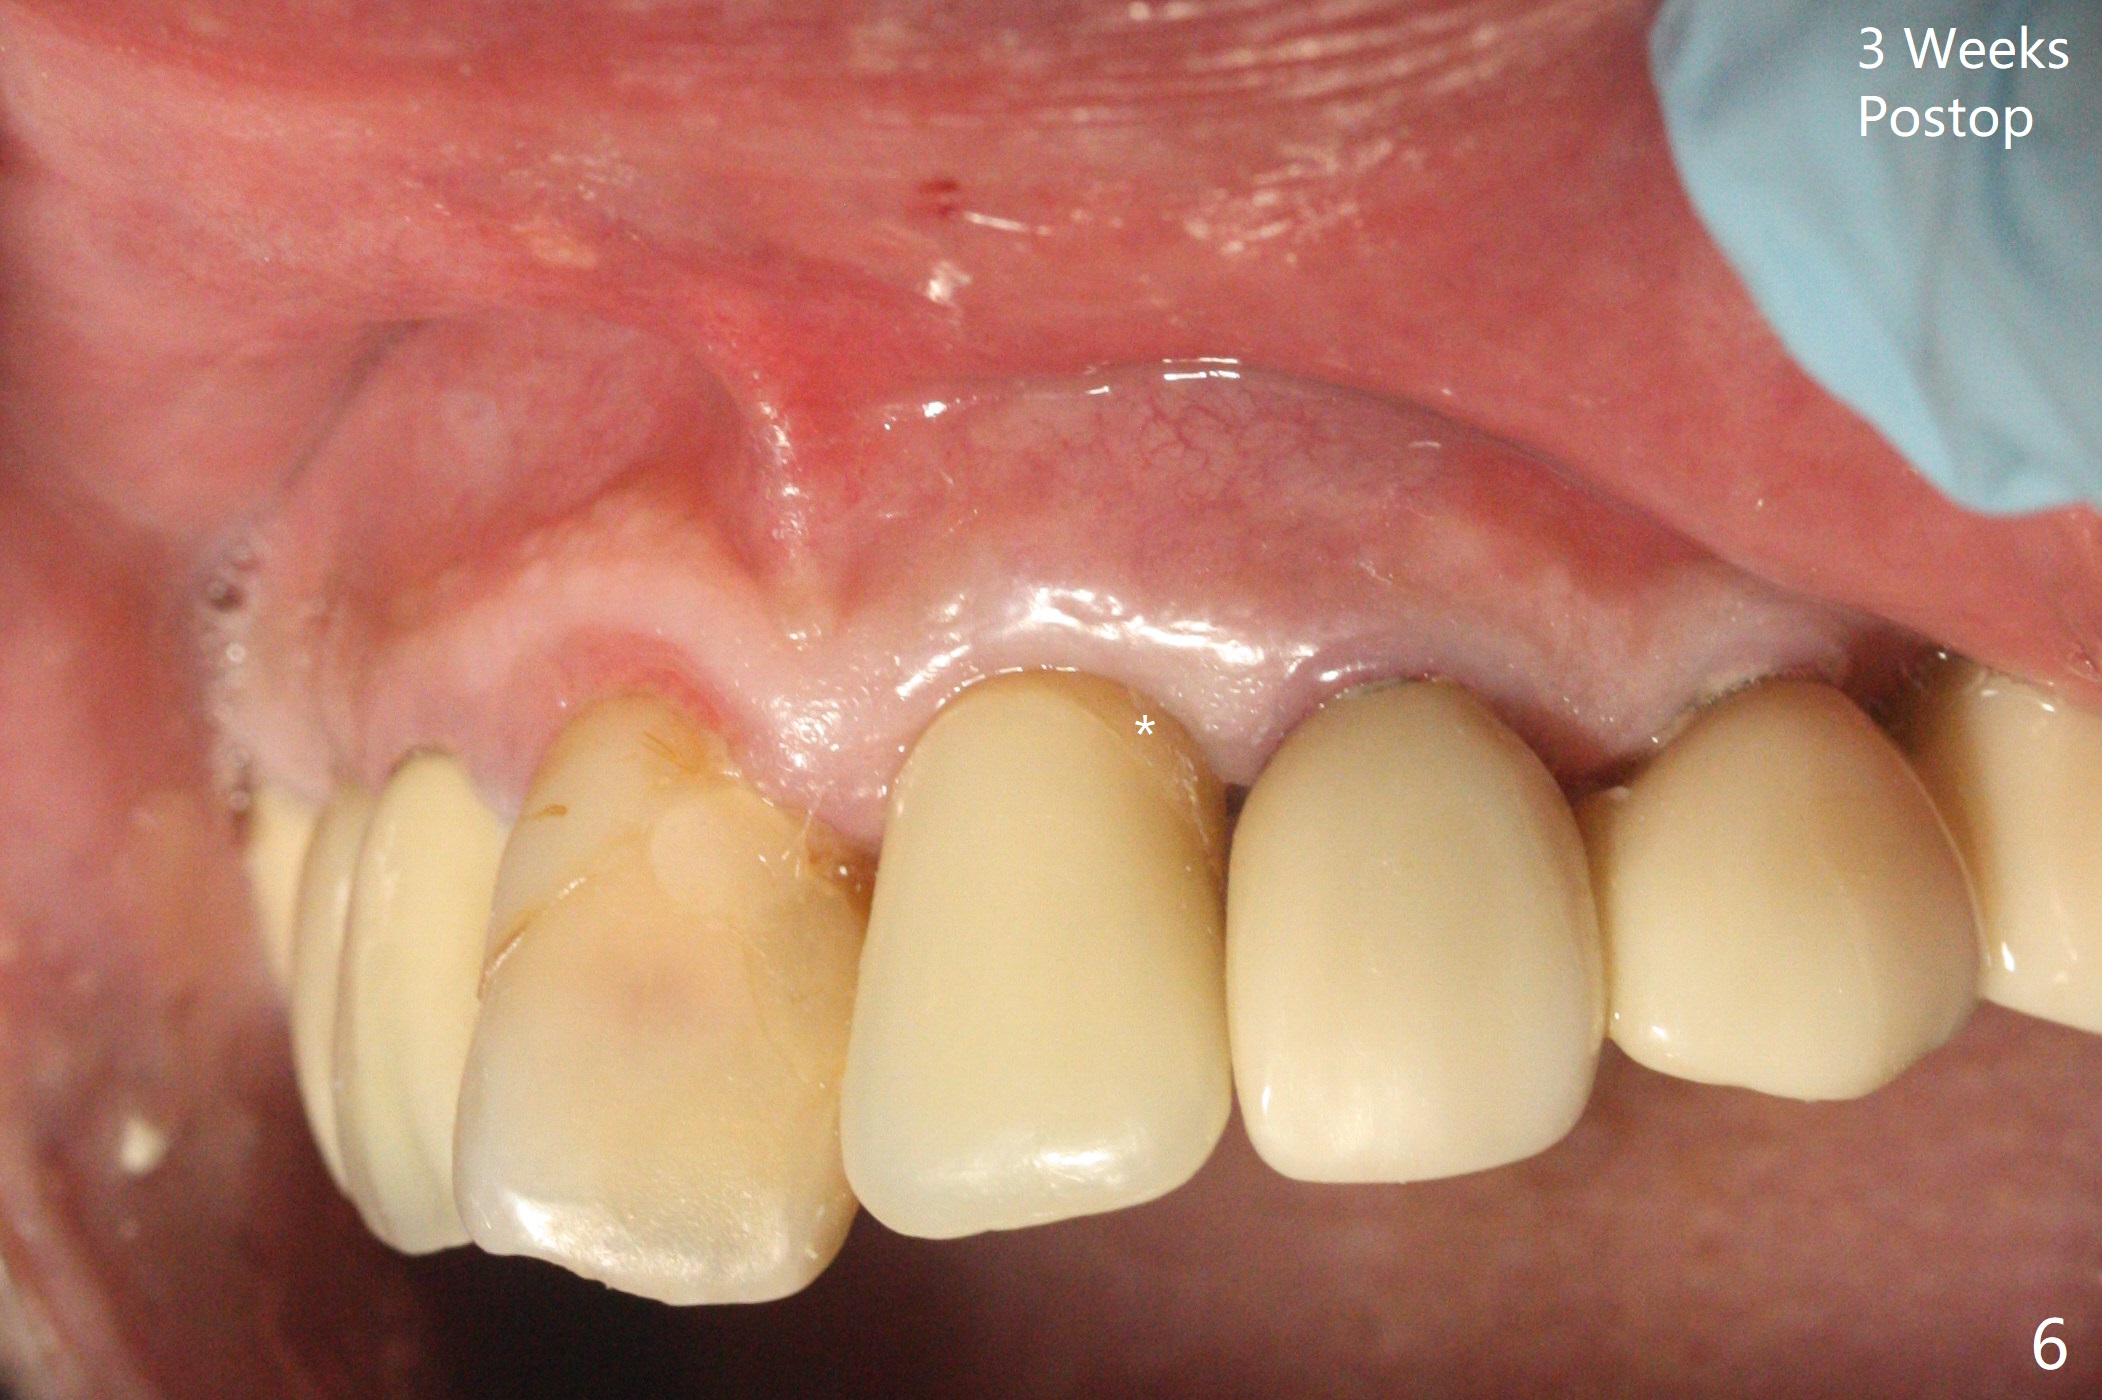

徒手种植不准确,需要反复调整,例如,为了避免接近侧切牙植体,中切牙钻洞开始于牙槽窝腭侧骨壁近中,结果接近切牙管(图一:红虚线),然后使用Lindamann bur移动钻洞,结果又太接近侧切牙(图二)。最后使用2毫米钻头试图改变钻洞方向,结果基台太接近侧切牙牙冠(图三)。而导板植入快,利索。 植入皮质骨骨粉(图四:*)后,制作临时牙冠。大约术后11天临时牙冠脱落(可能基台太短),病人没有及时复位,4天后牙槽窝愈合,可能变小,牙冠就位有些困难,造成颊侧牙龈发白(图五)。一周后牙冠又脱落,衬里后(图六:*)颊侧牙龈又显得饱满。